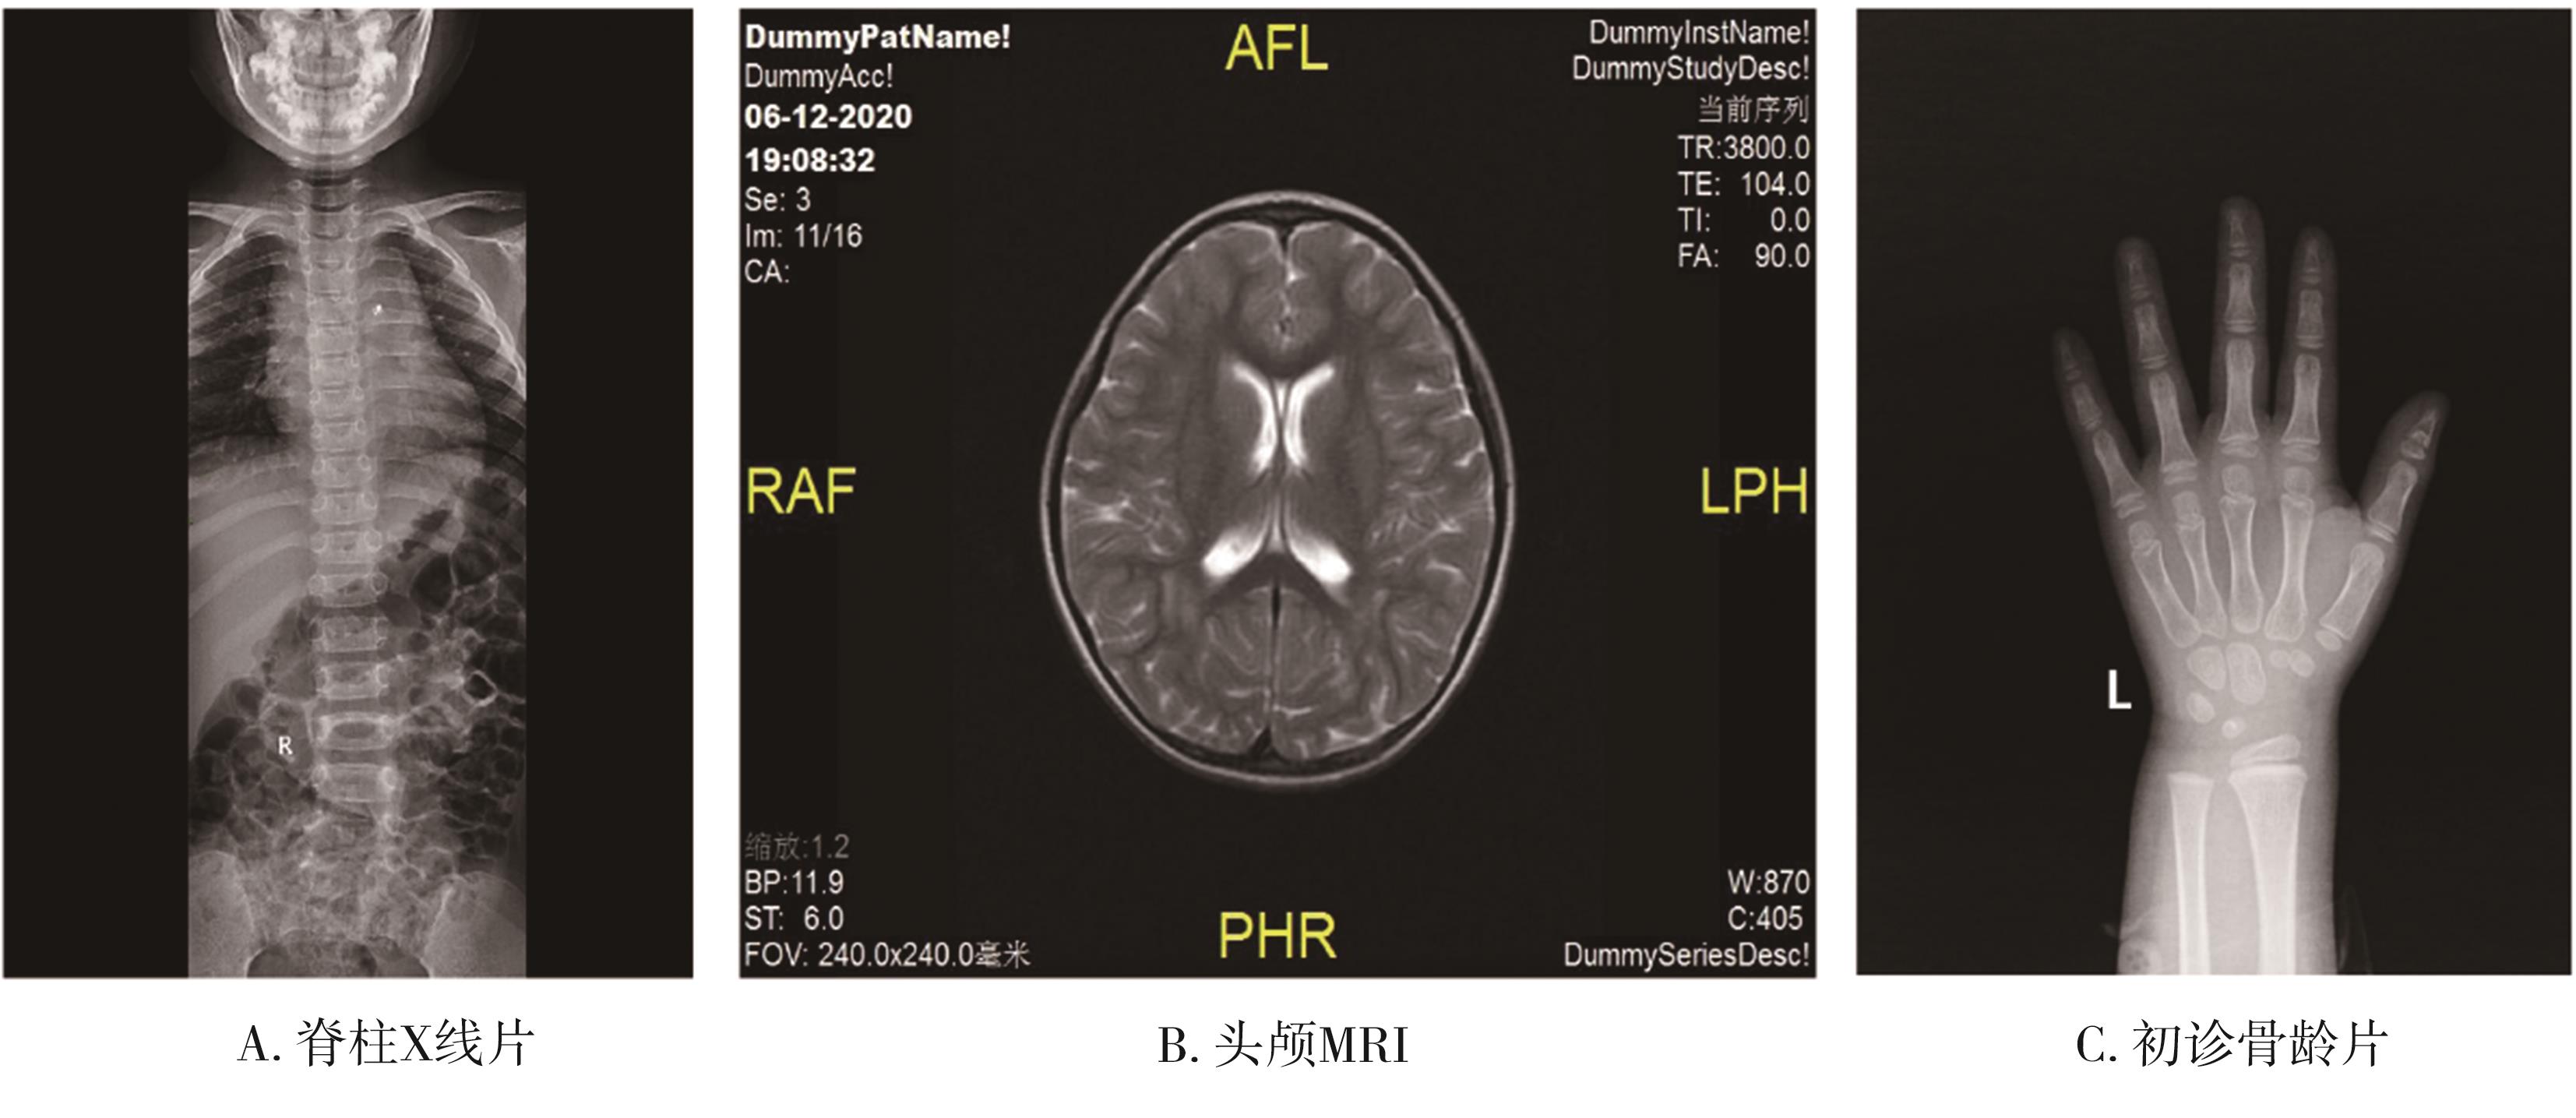

• 19p13.13微重复综合征致身材矮小及智力低下1例临床表型及遗传学分析

2023, 48(6):726-731. DOI: 10.13406/j.cnki.cyxb.003257

摘要 (56) HTML (23) PDF 2.23 M (154) 评论 (0) 收藏

摘要:

• 0+1

• 1+1

• 2+1

• 3+1